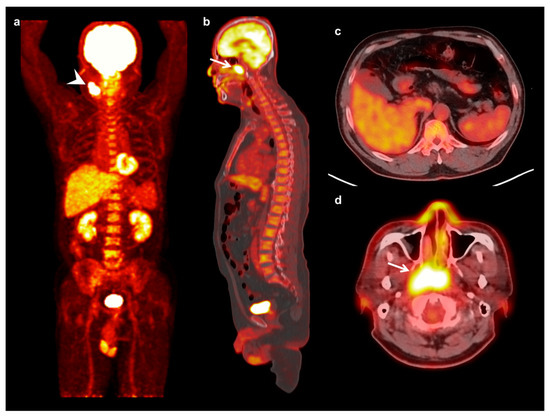

Figure 2.

Maximum intensity projection (a) and sagittal (b) FDG PET images and fused transaxial FDG PET/CT images (c,d) of a 57-year-old man with nasopharyngeal cancer. A 5.3 cm-sized mass in the right nasopharynx showed intensely increased FDG uptake (arrow) (maximum SUV 12.61, metabolic tumor volume 44.42 cm3, and total lesion glycolysis 237.65 g) with ipsilateral neck lymph node metastases (arrowhead). Serum CRP level, NLR, and PLR of the patients were 6.38 mg/dL, 5.10, and 243.01, respectively. On FDG PET/CT, markedly increased FDG uptake was shown in the bone marrow (BM SUV of 2.37 and BLR of 1.03). The patient was clinically diagnosed with T3N2, stage III, and underwent concurrent chemoradiotherapy. The cancer lesion progressed at 9.1 months after treatment.